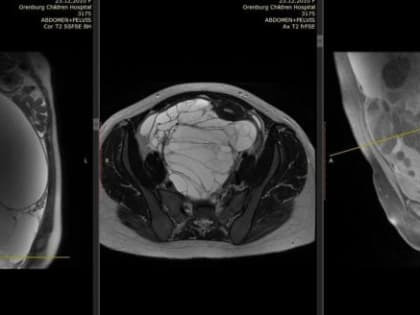

Уникальная операция на яичнике в Оренбурге

В Оренбургской детской клинической больнице успешно удалена гигантская опухоль у 13-летней девочки.